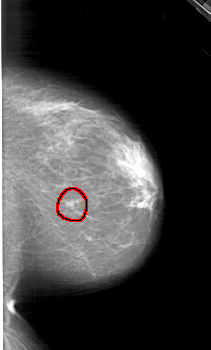

FILE: A_1299_1.RIGHT_CC.OVERLAY

TOTAL_ABNORMALITIES 1

ABNORMALITY 1

LESION_TYPE MASS SHAPE OVAL MARGINS CIRCUMSCRIBED

ASSESSMENT 4

SUBTLETY 3

PATHOLOGY BENIGN

TOTAL_OUTLINES 1

BOUNDARY